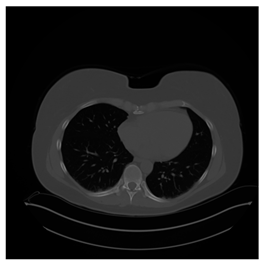

Table 5. Testing results of the Lung-PET-CT-Dx database.

Lung-PET-CT-Dx Computers 10 00152 i028 Computers 10 00152 i029 Computers 10 00152 i030

BPP0.05PSNR61.01Modified BPP0.052